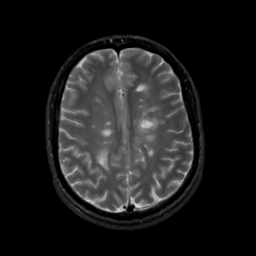

MR Study #10, April 28, 1991 -- Slice #34

[Home][Help][Clinical][Tour 1][Tour 2] Slice 34